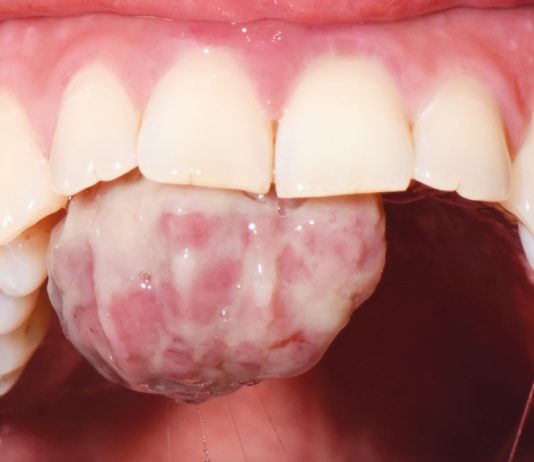

Trattamento chirurgico di un granuloma piogenico in gravidanza

Con il termine granuloma piogenico (GP) si intende una proliferazione tissutale in eccesso provocata da uno stimolo irritativo noto (1). Il principale fattore eziologico...